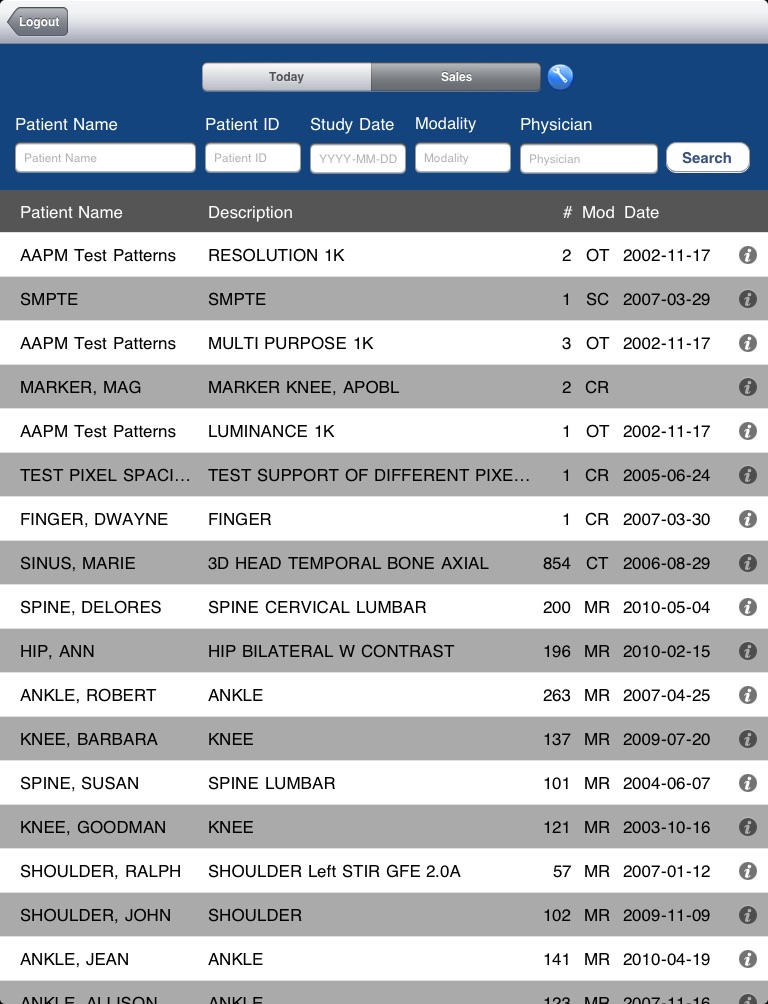

echoes for the iPad is your simplified access point to images on your echoes Server. With echoes, you can search and pull up studies from your server(s) and then perform simple image manipulations, including pan, zoom, and window/level. Flipping through images in a series is as easy as running your finger along a thumbnail strip. Choosing an image within a study is as simple as tapping it. Download echoes today and begin seeing your images in a whole new way!

A basic Today tab is provided that aggregates studies done today at all connected servers. Your home server will automatically connect at start-up and you can add a tab for any additional servers at any time by clicking the button next to the tab list. Your set of tabs will be recreated and reconnected at each sign-in. When backgrounded for an extended period of time, the app will lock to prevent unintended access to patient information. A software key is required once after initial installation of the app for authentication purposes and to ensure authorization to access patient health information.